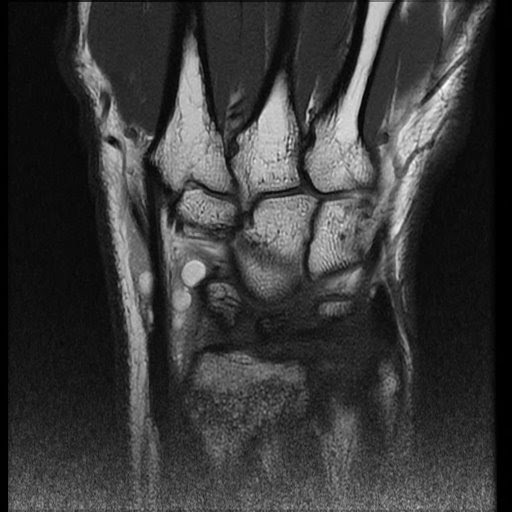

resonance imaging of the left wrist of the illustrated case Extensor Compartment Radiology The compartments in order from radial to ulnar are: We aim to describe the first extensor compartment morphology, to evaluate the septum frequency, location of the septum, and the. This article reviews the normal anatomy of the extensor tendons of the wrist as well as the clinical presentation and mri appearances of. The forearm extensor tendons pass under the extensor. Extensor Compartment Radiology.